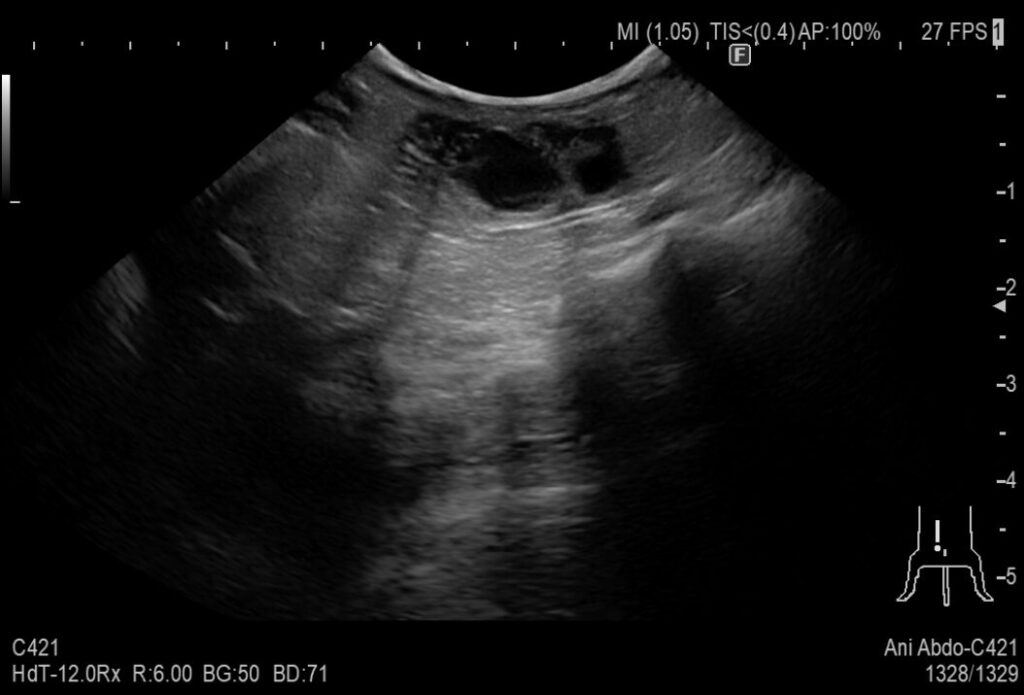

超音波検査では腫れた子宮が認められました。陰部からは大量の出血があり、貧血になっていたため緊急で手術を行いました。